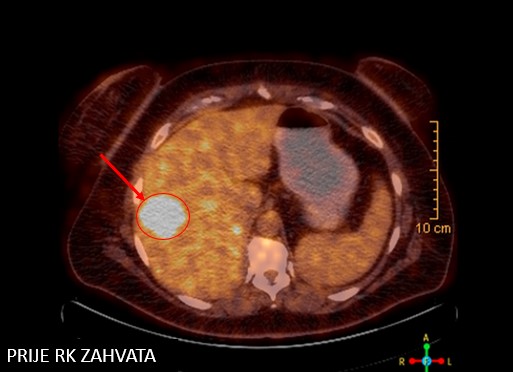

Bolesnica, rođena 1972.

Npl coloni sigmoidei (2019.)

Resectio coloni rectosigmoidei anterioris (3.4.2019.)

PHD: Adenoca gr I, pT3N1

Meta hepatis et lymphonodorum mediastini

Chemotherapia cum FOLFIRI (6x)

SABR meta hepatis solitaria (1/2020)

Metastasectomia hepatis (5.3.2021.)

PHD: metastatski adenokarcinom uz pozitivna 3 limfna čvora

SBRT meta hepatis et lymphonodorum mediastini (5. - 9.9.2022)

Rezultat – 44 mjeseca nakon RK

kompletna metabolička regresija tretirane lezije